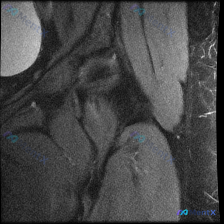

整理了一个髋关节MRI病例,先只放T2冠状位的影像分析。 核心信息: - 右侧髋关节MRI(T2冠状位) - 股骨头内侧近关节面下骨髓区:边界欠清的斑片状低信号影 - 关节间隙、髋臼、周围软组织无明显异常 用户最初问题是“盂唇病变”,但影像的核心发现是骨内异常信号。 大家第一眼看到这个低信号,会优先...